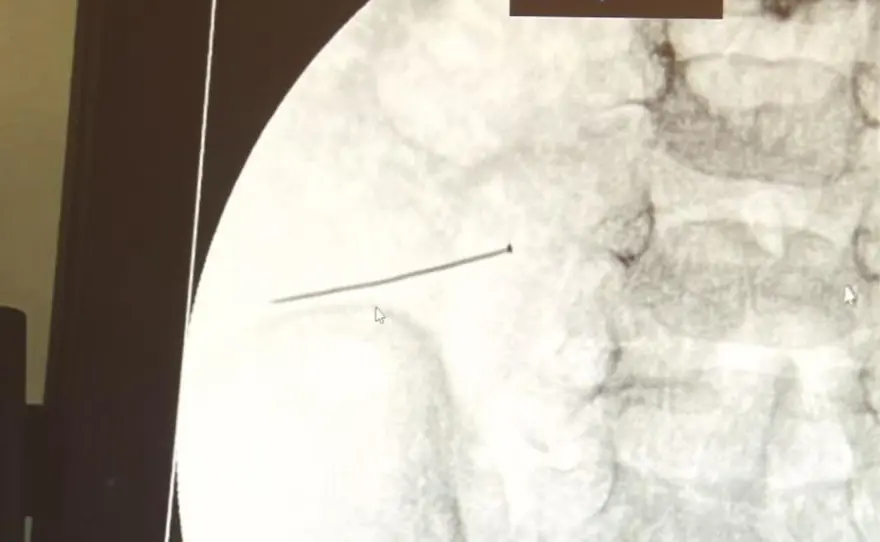

Hastanede yapılan tetkiklerde bebeğin ince bağırsağında yaklaşık üç santimlik toplu iğne olduğu ve bağırsağı deldiği belirlendi.

Çocuğun yuttuğu toplu iğne